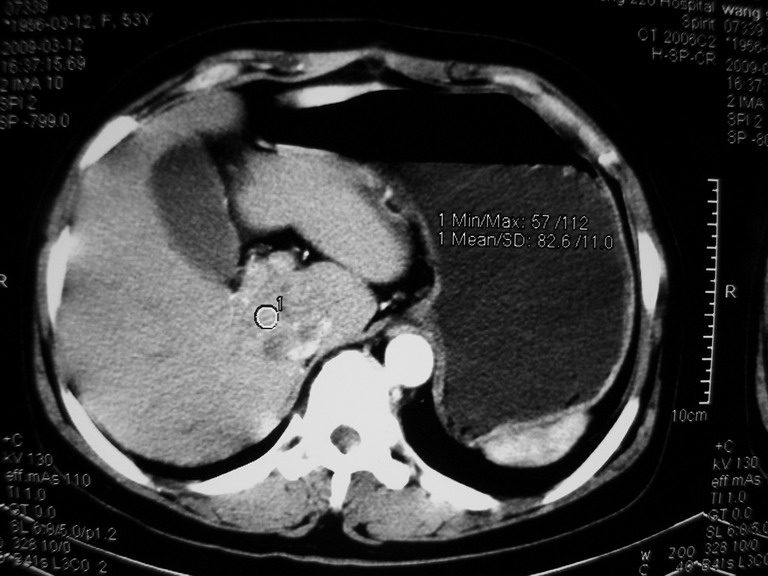

患者,女性50岁,上腹部不适2年余,既往多次腹部彩超未见异常,今日上午在我院查彩超发现肝右叶囊实性病变,外院辅助检查,afp,cea,ca199, 都在正常范围内,无肝炎史否认肿瘤史,生活在牧区

接着往下一贴看,有静脉期和延迟期,在看看和下腔静脉及十二指肠的关系,腔静脉内是不是栓子?

考虑肝右叶与尾叶交界区肝癌(部分外生),侵犯下腔静脉并下腔静脉瘤栓形成。

肝包虫病可能性大